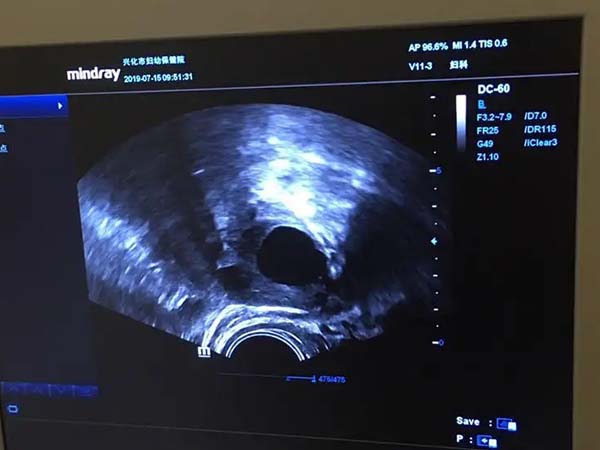

现实生活中,很多女性都会纳闷:为什么都是试管促排,可卵泡的数量差异会这么大呢?别人促排后两侧卵巢各有十来个卵泡,而自己每侧只有两三个,其实促排后卵泡少可能和下面几点有关: